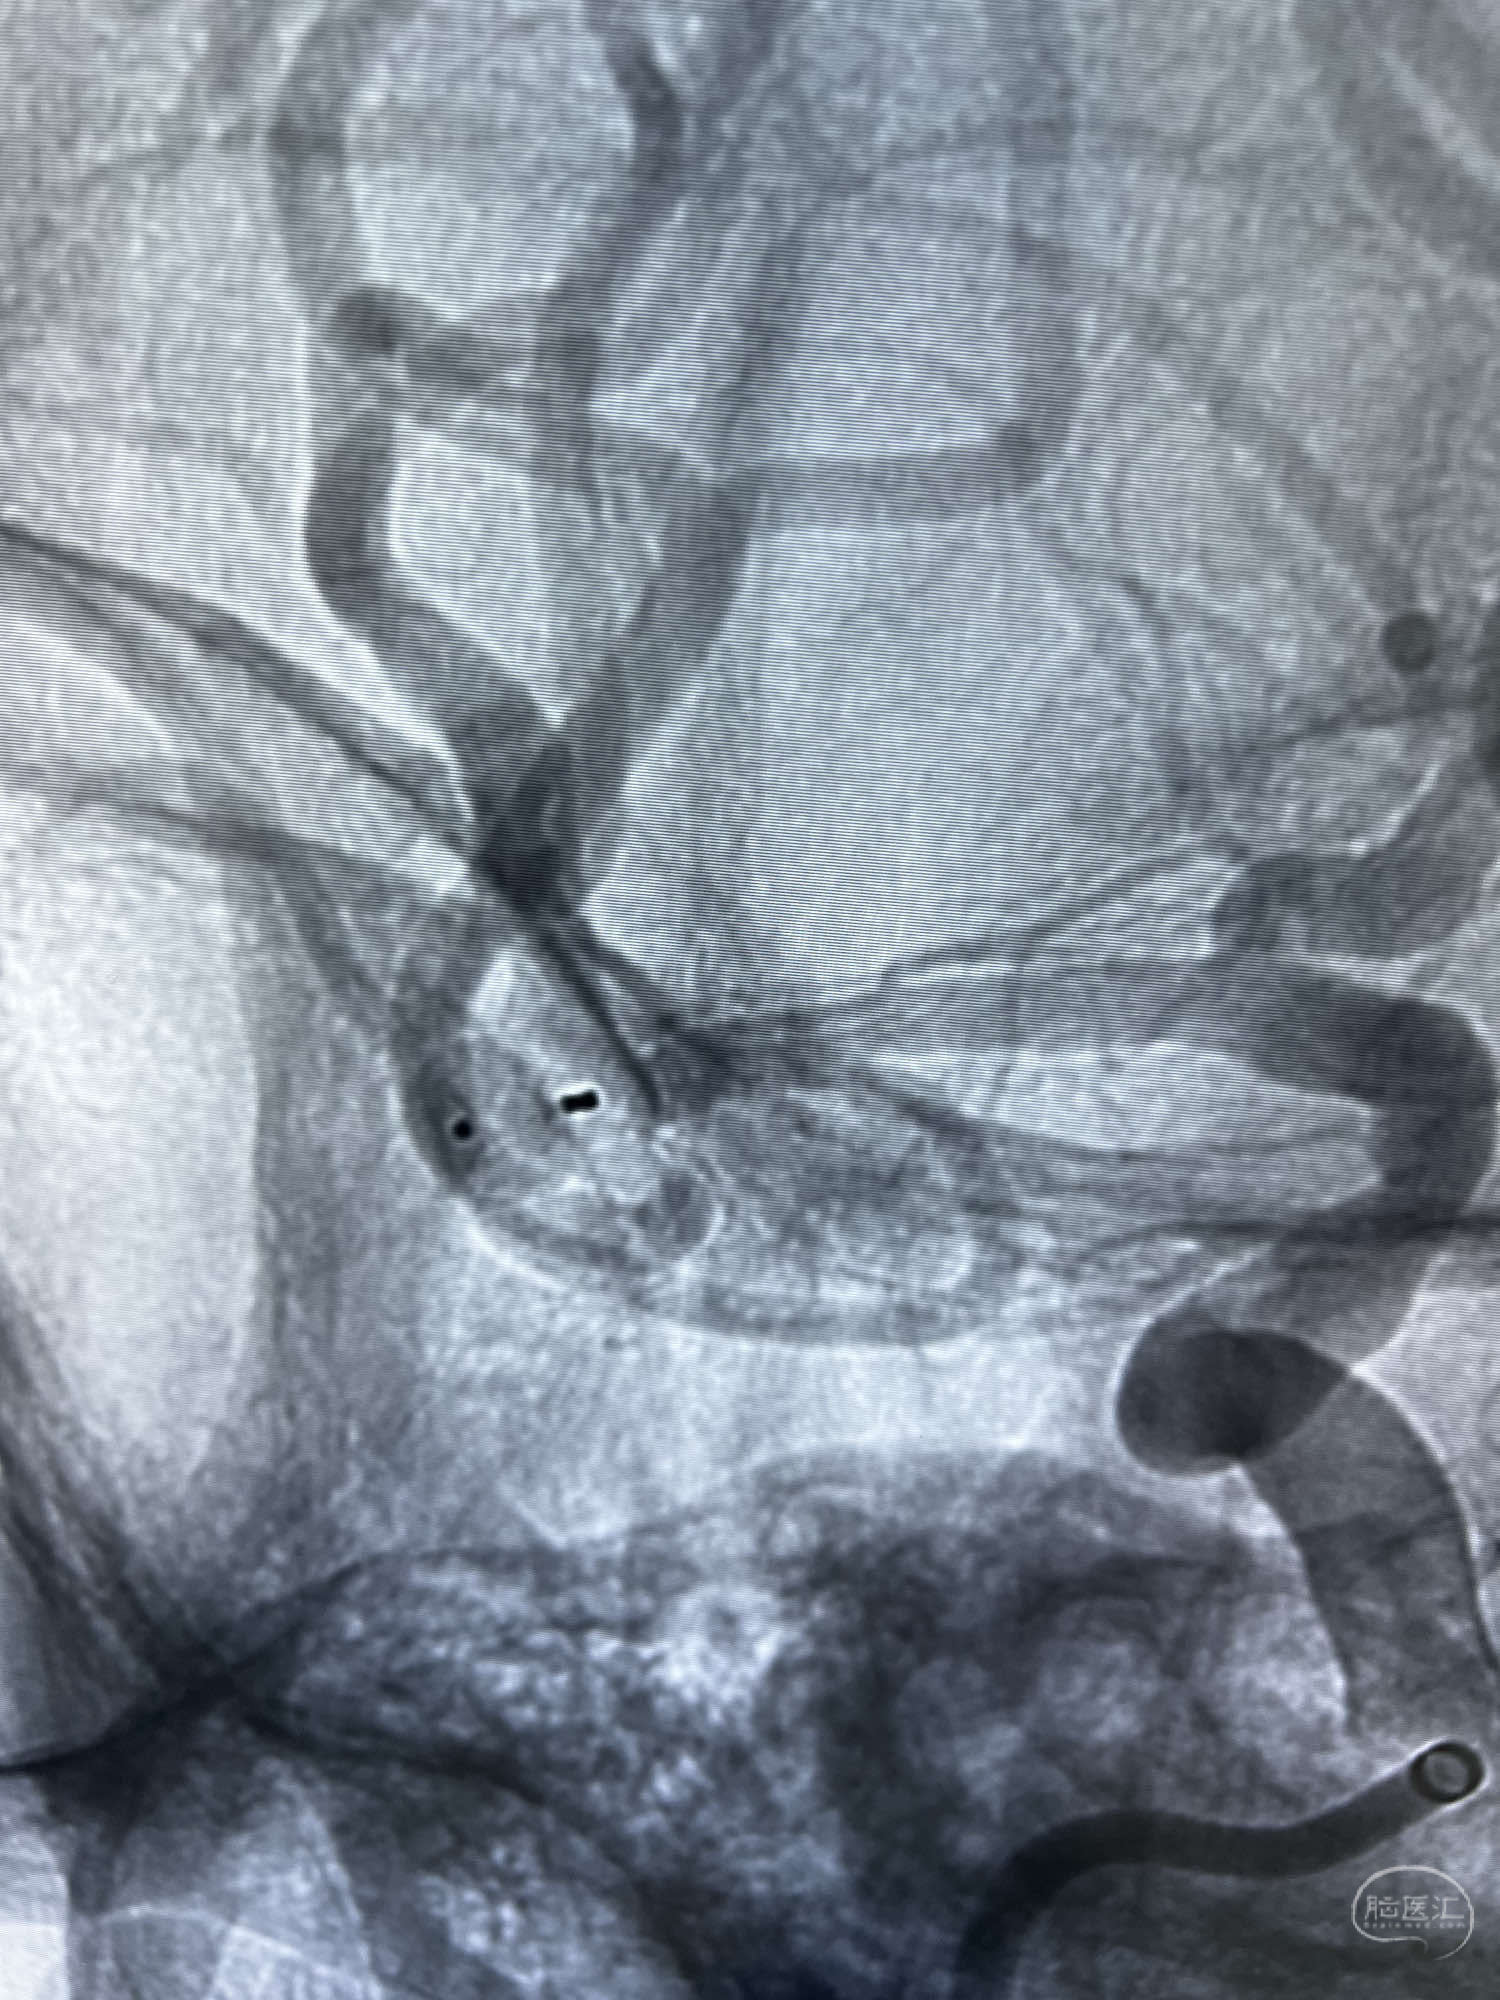

6F Neuromax➕6F115cm 心玮中间导管建立路径,sychro14微导丝➕VIA21超选至动脉瘤体内近中部,WEB5mmx3mm植入动脉瘤。

WEB瘤内扰流装置5mmx3mm经过“种子、萌芽、开花”三个阶段,打开后良好贴壁,动脉瘤内血液滞留,载瘤动脉通畅。WEB一步到位,通过瘤内扰流的方式起到栓塞动脉瘤的作用,避免了应用支架保护分支血管,简化了操作步骤,降低了术中血栓及出血的风险。